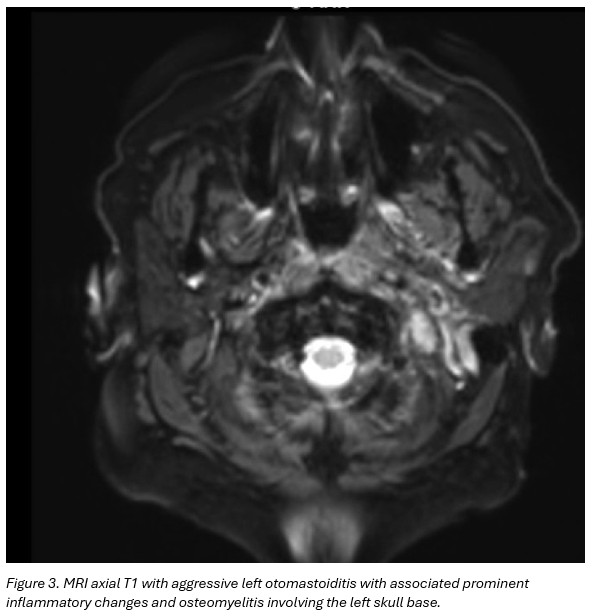

MRI brain and neck soft tissue with contrast: Findings suggestive of aggressive left otomastoiditis with associated prominent inflammatory changes and osteomyelitis involving the left skull base. No evidence for underlying neoplasm, or drainable fluid collection/abscess. No intracranial extension of disease. (Figure 3)

Diagnosis of SBO can be challenging due to its insidious onset and overlap with chronic otitis externa or media. Imaging modalities such as MRI and CT are crucial to delineate bone involvement and exclude abscess formation, while biopsy remains the gold standard for definitive microbiological diagnosis.3,4 In this case, CT-guided biopsy facilitated targeted antifungal therapy, underscoring the importance of tissue sampling in suspected fungal SBO.